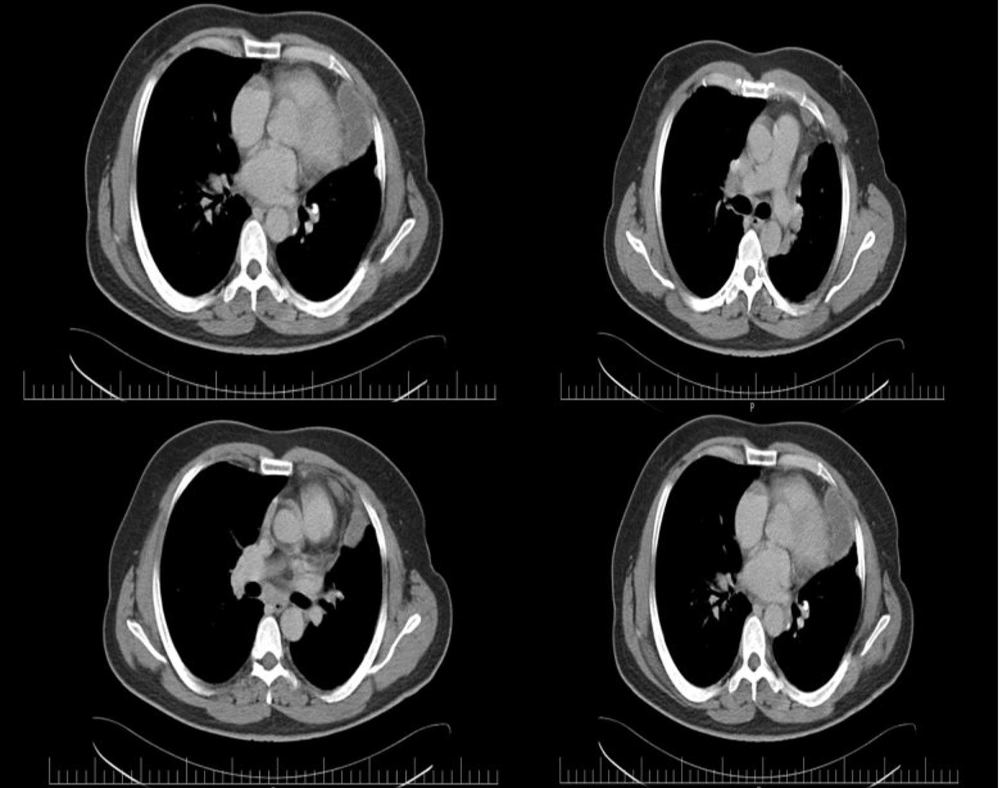

Based on the findings, the patient was referred for high-resolution chest tomography (HRCT) with contrast. The HRCT revealed multiple cystic areas with calcification in the pericardium, the largest measuring 7.50 × 5.19 cm. Additionally, a cystic area was noted on the left side of the mediastinum, measuring 5.75 × 5.42 cm (Figure 2).